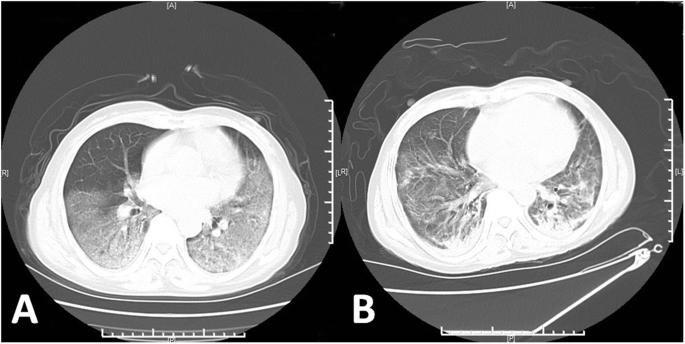

On January 28, 2020, a 49-year-old female patient was transferred to our hospital for further treatment after being diagnosed with COVID-19. At admission, She presented with fever, cough, sputum, and mild dyspnea. Her body temperature was 38 °C, blood oxygen saturation (SPO2) was 93% under ambient air, oxygen inhalation was immediately given by nasal catheter. After admission, levofloxacin and human immunoglobulin were injected into the veins, recombinant with human interferon a2b atomized inhalation. On the 5th day of admission, the disease deteriorated and her mental state was poor, body temperature was 38.8 °C, blood gas analysis: PO2 49 mmHg, PCO2 38 mmHg. She suffered from type I respiratory failure, which conformed to the diagnostic criteria of severe COVID-19 according to the COVID-19 health guidelines of China national health commission. On the 8th day, oxygen inhalation was given by oxygen storage mask (8 L/min), SPO2 was 93%, blood gas analysis: PO2 49 mmHg, PCO2 38 mmHg, Chest CT indicated multifocal ground glass opacities in both lungs with consolidation in partial lungs, which involving more than 75% of the lungs (Fig. 1a). On the 12th day of admission, the patient was anxious, agitated, Alprazolam was administered for sedation. Under high-flow oxygen inhalation (FiO2 90%, 50 L/min), SPO2 was 83 to 90%, blood gas analysis: PO2 55 mmHg, PCO2 44 mmHg, the oxygenation index<70 mmHg, which indicating poor oxygenation status, and non-invasive positive airway pressure ventilation was immediately performed. On the 14th day of admission, SPO2 was 90%, blood gas analysis: PO2 48 mmHg, pCO2 37 mmHg, under the condition of non-invasive positive airway pressure ventilation, FiO2 70%, which revealed poor and difficult to ameliorate hypoxemia, mechanical ventilation became imperative. The patient progressed to critical cases and was transferred to intensive care unit (ICU), mechanical ventilation was performed by orotracheal intubation, ventilator conditions: Volume Control ventilation, VT 240 ml, VF 15 times/min, FiO2 100%, PEEP 10 cm H2O, prone position ventilation was performed at the same time. After intubation, maintaining the use of propofol and midazolam for sedation, SPO2 rose to 95% and hypoxemia improved. On the 16th day of admission, the patient’s SPO2 was difficult to maintain with poor oxygenation index and high airway platform pressure, salvage VV-ECMO therapy was performed. Under the guidance of B-ultrasound, the right femoral vein was inserted into the inflow cannula, the right jugular vein was inserted into the outflow cannula, the venous cannula was 20F, the arterial cannula was 17F, the depth of venous cannula was 43 cm, and the depth of arterial cannula was 14 cm. Initial ECMO parameters: speed 3200 rpm, flow 5 L/min, Sweep gas 3 L/min, FiO2 70%. Coordinated ventilator parameters: Assist-Control ventilation, VT 210 ml, VF 18 times/min, FiO2 40%, PEEP 12 cm H2O. Reviewed blood gas analysis: PO2 84 mmHg, PCO2 46 mmHg, oxygenation index improved significantly after ECMO. During the treatment of ECMO, deep sedation was performed and heparin was continuously pumped to maintain activated partial thromboplastin time (APTT) being 40–60s. On the 19th day of admission, support condition of ECMO for the patient was still high, ECMO could not be removed in a short time, and the lung compliance was poor. Chest radiograph showed increased multiple patchy density shadows in both lungs (Fig. 2a). We decided to coordinating prone position ventilation to improve pulmonary ventilation-to-perfusion ratio. On the 22th day of admission, bronchoscopy showed: a little white sputum could be seen in the main bronchus, and slightly swelling, hyperemia could be seen in the grade 1–4 bronchial mucosa of both lungs. On the 27th day of admission, the patient was tested negative for SARS-CoV-2 nucleic acid by the fluorescence quantitative RT-PCR for two consecutive times. After the withdrawal of sedative drugs, the patient was conscious, had a firm handshake, we stopped the ventilator, ECMO parameters was adjusted: speed 3600 rpm, flow 4 L/min, Sweep gas 3 L/min, FiO2 70%, oxygen was inhaled through the endotracheal tube whit high-flow oxygen therapy (FiO2 45%, 40 L/min). After observated for 30 min, blood gas analysis: PO2 71 mmHg, pCO2 45 mmHg, heart rate was 83 beats per minute, breathing rate was 25 times per minute, and blood pressure was 136/63 mmHg, the endotracheal tube was removed, awake ECMO was performed. Treatment strategies during awake ECMO stage: 1. Strengthen the monitoring and management of bleeding and thrombosis, monitoring the levels of hemoglobin, platelets, APTT and fibrinogen, and set the corresponding target values to be 90 g/L, 100*10^9/L, 40S, 2.0 g/L respectively, supplement the substrate by transfuse some components of blood if failed to meet target values. 2. Pulmonary rehabilitation: prone position or high lateral lying position was adopted for drainage to promote lung recruitment, and a large dose of ambroxol and acetylcysteine were used to dispersing phlegm. 3. During the awake ECMO period, patients had intermittent anxiety and delirium, enhanced psychological counseling, quetiapine and haloperidol were given to fight anxiety and delirium. 4. Combined Piperacillin tazobactam, Datomycin and Voriconazole to fight infection. 5. Strengthen liquid management and nutritional support therapy. On the 35th day of admission, the patient’s oxygen saturation could be maintained at 98%. After re-examination of chest radiograph (Fig. 2b), the patient was evacuated from ECMO. Reexamination chest CT on March 6, 2020 indicated the ground glass opacities absorbed, and leave some fibrotic stripes (Fig. 1b). After further treatments of anti-infection, pulmonary rehabilitation, nutritional support, psychological counseling and physical rehabilitation, the patient recovered and was discharged on March 15, 2020.